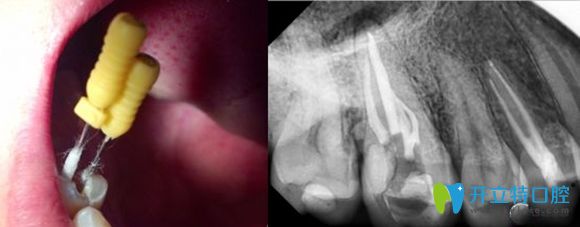

牙齒根管治療過(guò)程中圖片

根管治療后的X線片影像圖